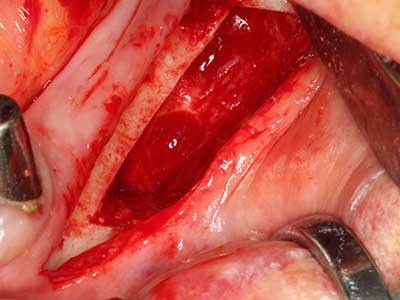

Abb. 18: Präparation eines Kortikalis-Deckels mit der Piezo-Knochensäge (Piezomed, W&H).

Abb. 19: Operationssitus nach Neurolyse und Osteomentfernung.